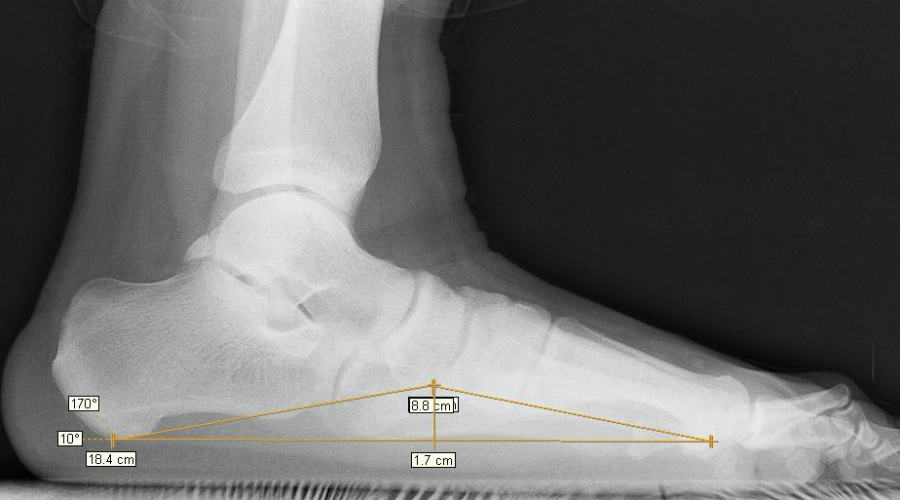

В здоровой стопе природное соединение подвижных костей составляет два свода. Они выполняют амортизирующую функцию. Врожденные пороки или внешние факторы могут привести к тому, что стопа становится плоской и соприкасается с поверхностью — соотвественно, амортизационная функция перекладывается на другие части тела, которые не предназначены для таких нагрузок. С этого и начинаются настоящие проблемы для всего организма.